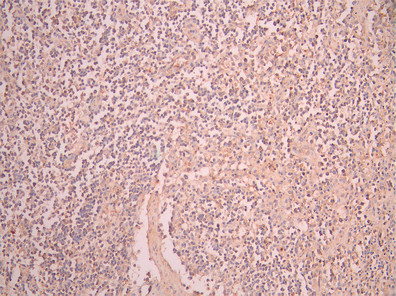

IHC image of CSB-RA004793MA1HU diluted at 1:50 and staining in paraffin-embedded human lymph node tissue performed on a Leica BondTM system. After dewaxing and hydration, antigen retrieval was mediated by high pressure in a citrate buffer (pH 6.0). Section was blocked with 10% normal goat serum 30min at RT. Then primary antibody (1% BSA) was incubated at 4°C overnight. The primary is detected by a Anti-Human lgG, Fcy Fragment Specific labeled by HRP and visualized using 0.05% DAB.